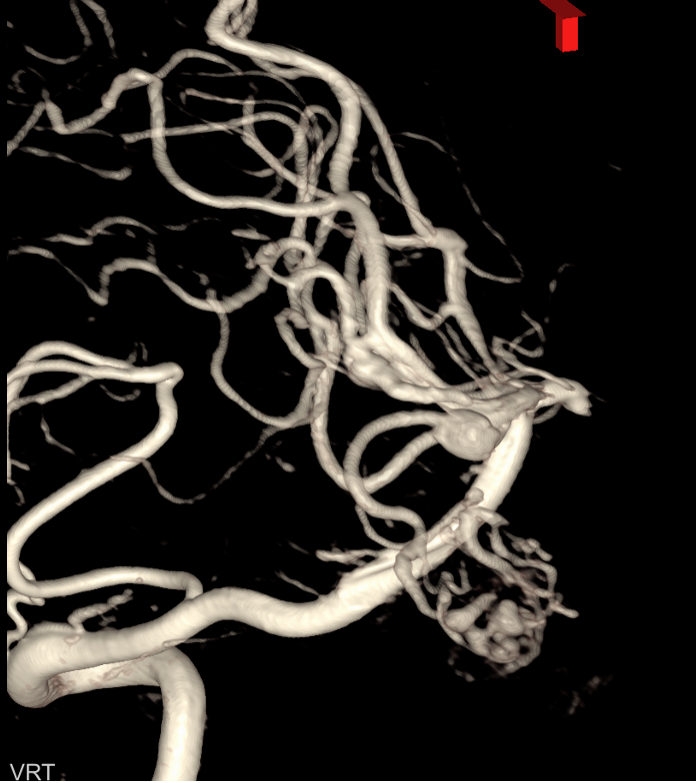

入院后脑血管造影检查提示:右侧颞叶动静脉畸形,由右侧大脑中动脉两分支血管参与供血,右侧大脑后动脉一分支血管参与供血,畸形团大小约1.1*1.3cm,通过侧裂静脉经皮层静脉引流入上矢状窦前部;并可见右侧大脑后动脉供血畸形团的分支血管血流相关性动脉瘤两枚。